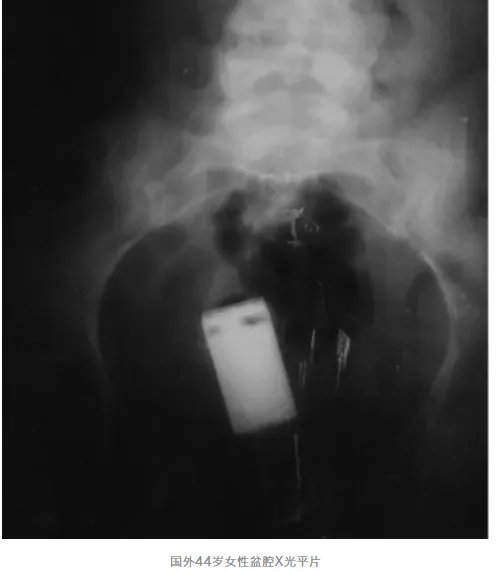

44岁女性不小心把电池卡在了阴道。但是人可能是因为怕尴尬,就这样被“夹住”的电池在体内保持了2个月,终于忍不住去了医院。这时她出现全身症状,发烧38.5℃。同时阴道排出大量绿色分泌物。阴道内电池,稍作移动,患者就非常难受,并且引起阴道快速出血。最后,吊瓶挂上抗生素抗感染。配上阴道后穹窿手术,终于将电池取出。取出的电池,已经被阴道“腐蚀”的不完整,并且存在有毒物质泄露。答案往往没那么简单国外曾报道11年期间诊治的48例结直肠异物,其中78%与直肠性刺激有关。国内也曾报道,12例中老年男性的直肠异物,均因“紫薇”导致。看起来,这些行为都是为了自我满足。实际上,这些行为反应的是多方面的原因。据调查,直肠异物行为与性取向有关。还有些,真的是出问题了,如由于泌尿系感染,瘙痒难耐,用异物止痒,导致异物脱手,进入到膀胱。背后的风险你要知道首先,手术和麻醉,本身对身体就是一种伤害。上述6个例子,除了小女孩外,都用了手术刀剖肠破腹。本想释放压力,结果可能赔了夫人又折兵。再者,异物的类型,和牵扯的部位,可能带来严重不良后果。第一个例子,其实很为这位患者庆幸,他及时前去医院就诊,去的还是技术高超的中山大学一附院。一个玻璃杯,若是不能及时取出,或者是出现碎裂的情况,很容易引起肠穿孔。肠穿孔的后果比你想象的要大得多,尖锐的玻璃碎片会划伤周围的器官,肠道内的细菌也会从肠道中跑出来,引起感染性腹膜炎,严重者可能会出现休克甚至危及生命。膀胱异物,易引起尿频,有时也会出现血尿,如果不幸尿路堵塞,就会造成尿潴留。阴道异物,常常会持续出现有刺激性味道和血性的白带。为了避免受到没必要的伤害,不要乱塞。没必要真的没必要